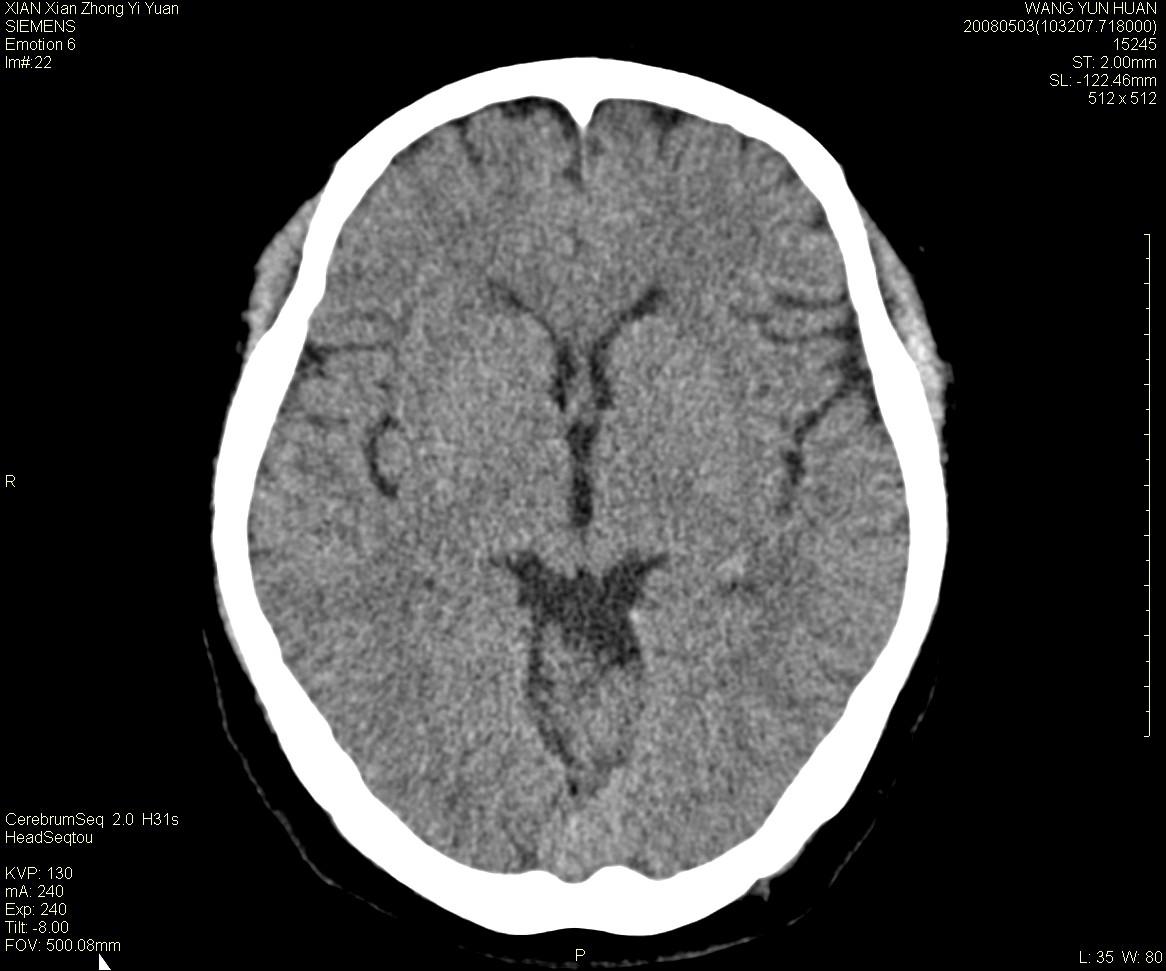

标题: CT13219:(补充强化)请会诊,患者女,60岁,头晕,大家看 [打印本页]

标题: CT13219:(补充强化)请会诊,患者女,60岁,头晕,大家看

病灶显示轻度强化,ct增加4hu左右,大家看是什么肿瘤.

强化后动脉期及延迟2分钟,五分钟图像

小脑蚓部囊型肿块,内有实性结节及钙化点。增强后囊壁及结节轻度强化。

考虑蚓部星形细胞瘤(ⅱ级可能性大)。

小脑蚓部肿块,周围无明显占位效应及水肿带,增强轻度强化,考虑低分级星形细胞瘤。